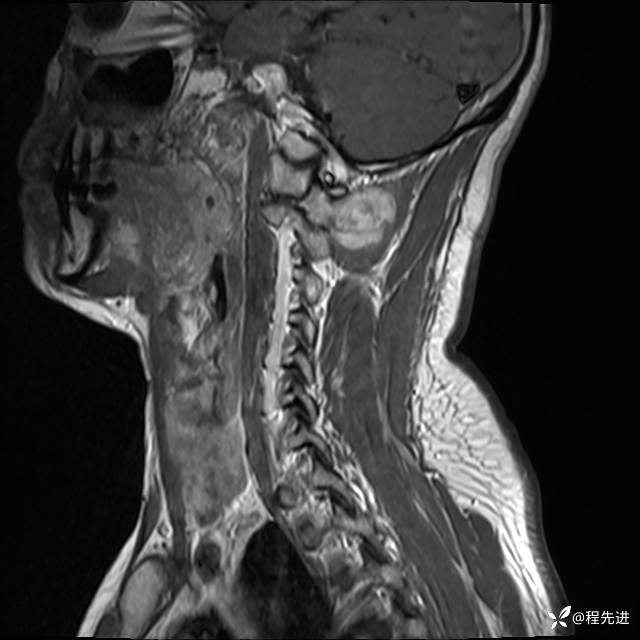

MRI平扫+增强:

T1: